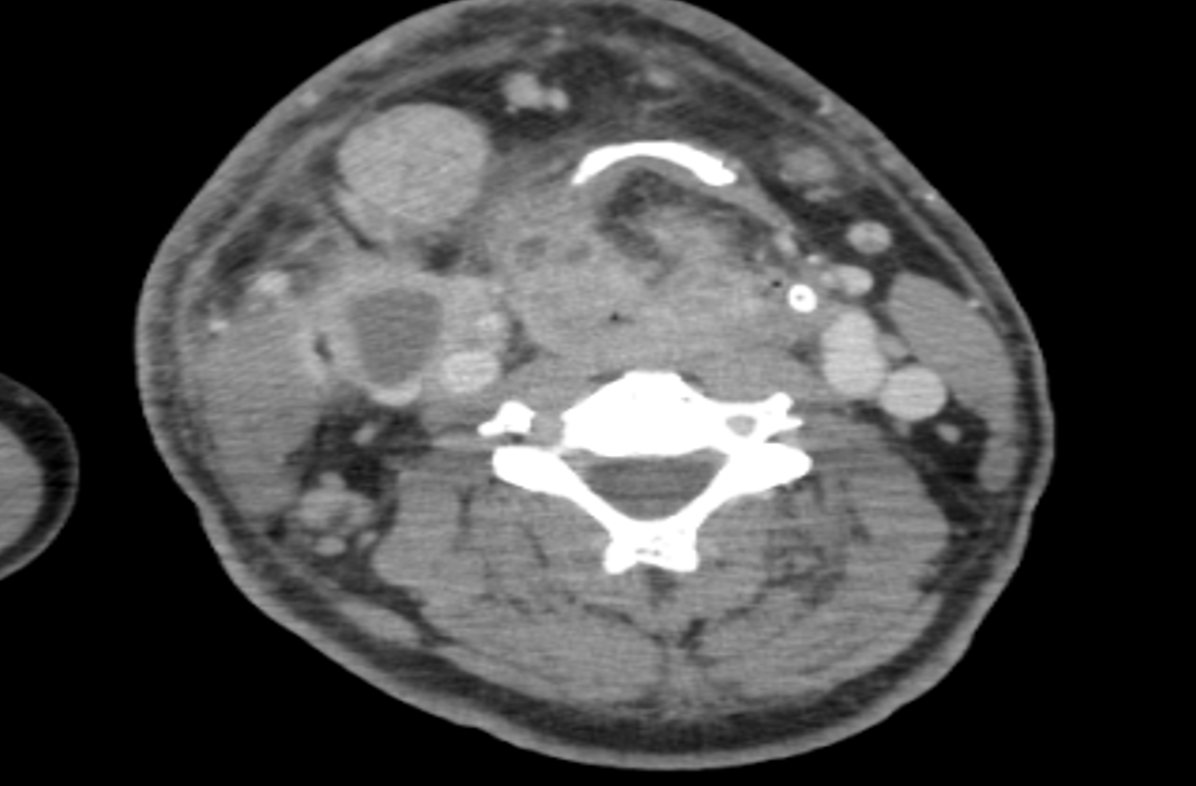

• TDM cervico-thoraco-abdomino-pelvienne (28/07/2025) : masse laryngée hétérogène, mal limitée, de l'os hyoïde à la région thyroïdienne, infiltration locorégionale (épiglotte, segment œsophagien en regard) et lyse bilatérale des lames du cartilage thyroïde. Adénopathies latéro-cervicales droites nécrotiques en logettes, conglomérat d'environ 66 mm en reconstruction coronale. Autres adénomégalies latéro-cervicales bilatérales non remaniées (jusqu'à 11 mm petit axe à droite). Pas d'atteinte suspecte thoraco-abdomino-pelvienne (Fig. 1).

Fig. 1 : TDM cervico-thoraco-abdomino-pelvienne